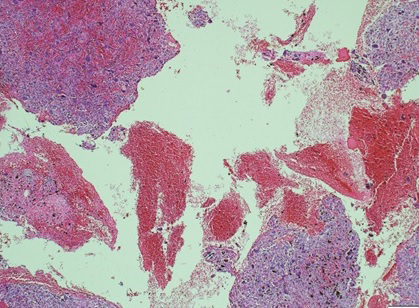

The fracture was first approached via an anterolateral approach to the distal fibula in which the fibula fracture was fixed by a 1/3 tubular plate and screws. This was followed by a complete curettage of the lesion and bone grafting with cancellous bone chips allograft. Finally, the tibia fracture was fixed by minimally invasive percutaneous osteosynthesis (MIPO) technique using 3.5mm locked plate medially (Figure 2). The excised bone material was then sent for histopathological examination which confirmed a non-ossifying fibroma with secondary aneurysmal bone cysts (Figures 3- 5).

Figure 5 Histopathological slide of the lesion-high-power magnification demonstrating blood-filled spaces consistent with secondary aneurysmal bone cysts.

The diagnosis is usually incidental during radiological evaluation for other reasons.4 Due to its characteristic radiological appearance, pathological confirmation is usually not necessary.5,7 This is especially true when the lesion demonstrates characteristic features such as a longitudinal growth pattern, lobulated and bubbly appearance with sclerotic border, and intact cortex.7 If however, any of these features is breached or in complicated cases, biopsy may be indicated.7 Histologically, the lesion reveals storiform fibrous tissue with spindle cells, multinucleated giant cells, hemosiderin and xanthoma cells.8  Secondary aneurysmal bone cysts are usually not present in the primary lesion. The presence of such changes is probably attributed to the complicated pathological fracture which results in bleeding and the formation of blood-filled spaces.7